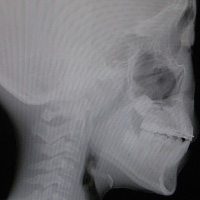

歯の本数や位置、上下顎骨の位置などを調べるために、レントゲン、セファロ、診断用模型を製作するための歯型、かみ合わせの型を採ります。